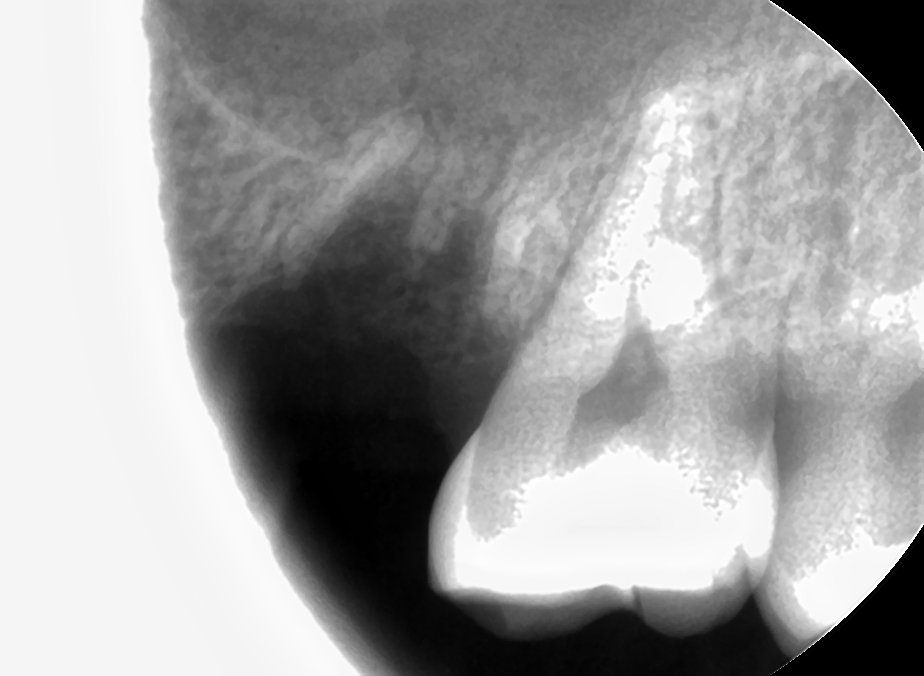

CT 영상(초진)과 standard x-ray 사진(팔라탈 루트 발치 후)

중간에 엑스레이 찍어서 남은 치근 위치 확인하고 EL3C로 다 꺼냈는데 상악동 누공이 너무 커보인다. 아마 심리적인 요인으로 더 커보였을 것이다. 돌이켜보면 그렇게까지 크지는 않았을지도? 치과엔 콜라겐 플러그나 큐탄플러스트, 써지셀 그런 건 없는 것 같다 못봤어. 그래서 생각나는 건 플랩 열어 1차봉합 해주는 방법. 얼른 블레이드 달라고 해서 플랩 열고(근데 여태 플랩 안 열고 뭐했니?) 페리오스틸엘리베이터로 박리 넓게 해준 다음 골막 살살 감장절개 해서 땡겨 구개측에 1차봉합 해줬다. 깔끔하지 못해서 영 마음이 안 좋고 해놓고도 마음이 콩닥콩닥 해서 DSLR 사진 찍어 놓고 대표원장님께 보고드렸다. 대표원장님께서 협측에 감장절개 해도 구개측까지 안 당겨져서 1차봉합이 잘 안될 땐 구개측에 horizontal하게 인시전 넣어 플랩 땡겨와 수쳐할 수 있다는 팁도 알려주셨다.(구개측 치은에 일시적으로 defect 생긴 거는 금방 치유된다고)